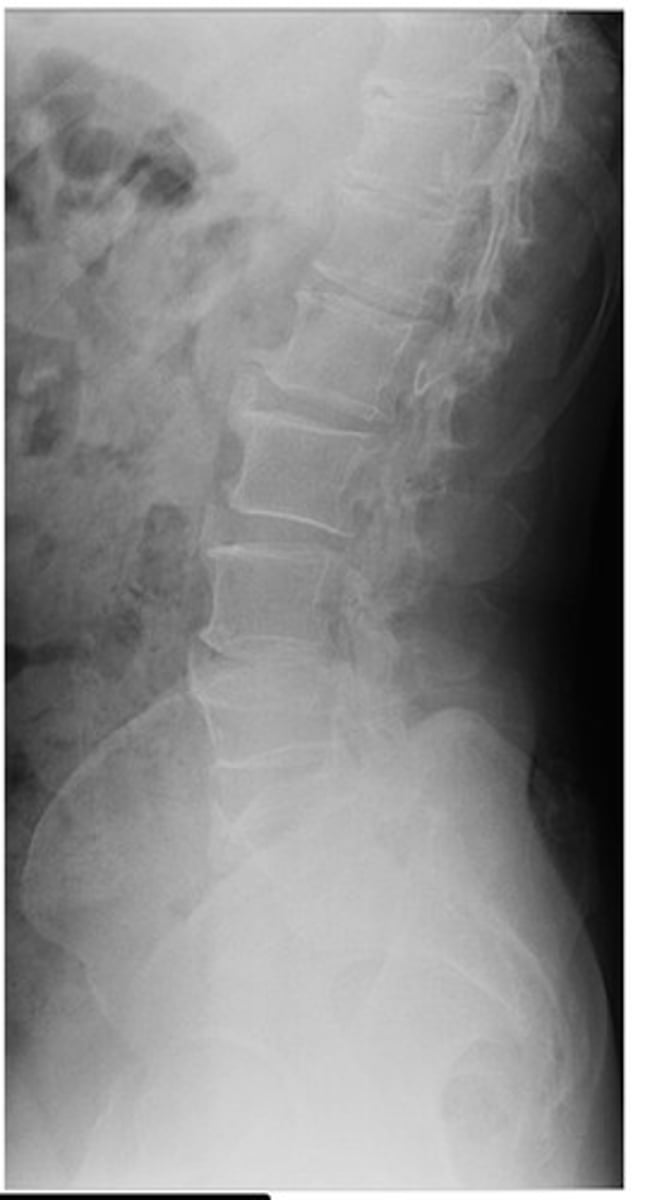

What diagnosis is this?

Non-marginal enthesophytes